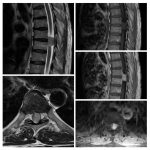

Neurosurgery and neuroradiology always go hand in hand. This little weekly activity is going to enhance the scan reading skills of our audience in an interactive way. Waiting for the answer for a week will keep the curiosity alive and will keep our target audience hooked to the website. It will prove to be a seamless share of knowledge and reading skills.

Dr. Saqib Kamran Bakhshi started the PANS Weekly Image Challenge in 2022, and his creativity and efforts made it a popular activity; engaging trainees and consultants in Pakistan and abroad.